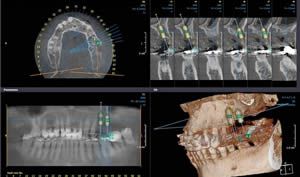

Sowohl die eigentliche Insertionsstelle von Zahnimplantaten als auch die prothetische Gestaltung des späteren Zahnersatzes ist auf Basis von DVT-Aufnahmen möglich und kann individuell auf die Anatomie des Patienten abgestimmt und darauf ausgerichtet werden.

Durch die detaillierte Darstellung der knöchernen Strukturen mit dem Verlauf von Nerven und Gefäßen können dabei Risiken einer Schädigung sicherer vermieden werden. Somit sind schonendere Implantationen durchführbar. Darüber hinaus ermöglicht es die DVT, das vorhandene Knochenangebot optimal auszunutzen.